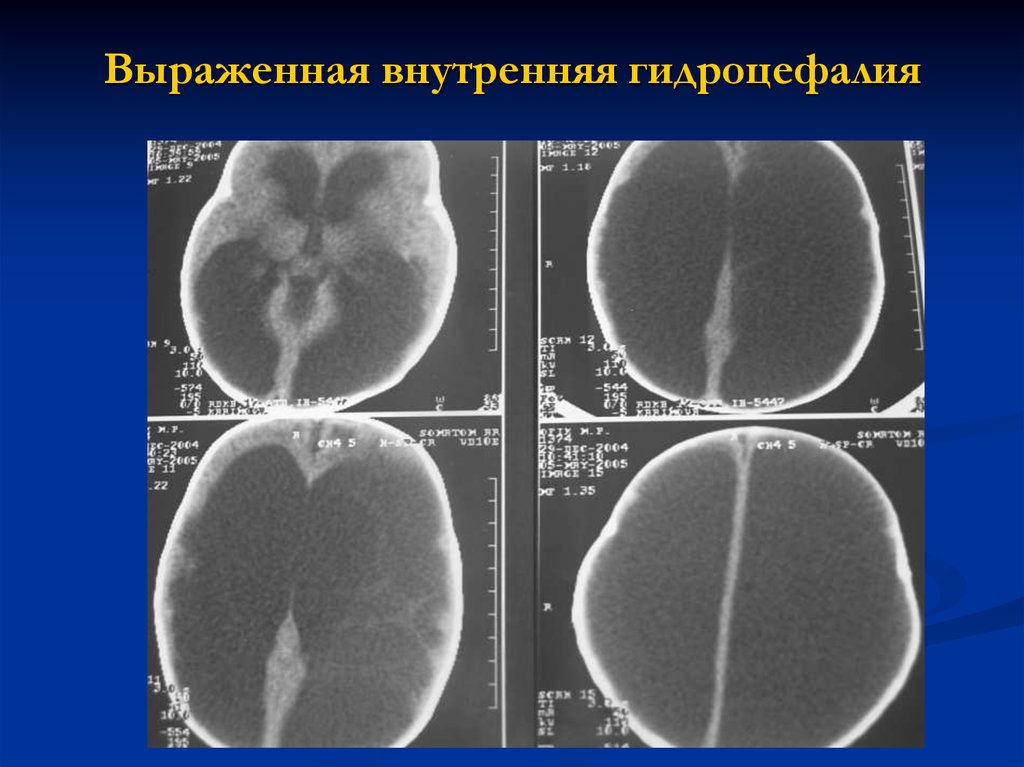

Признаки умеренно выраженной наружная

Признаки умеренно выраженной наружная 113 фото